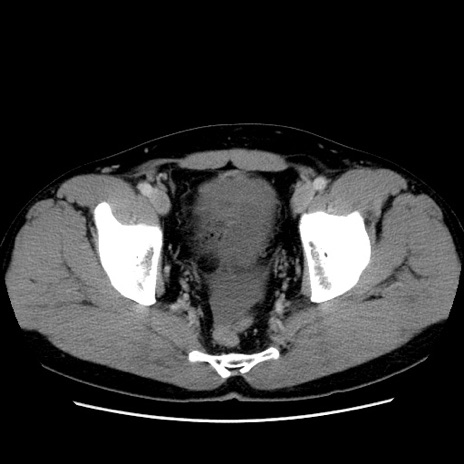

症例4(横断像)

【症例】30歳代男性

【主訴】腹痛、嘔吐

【現病歴】昨晩から突然の腹痛あり、その後嘔吐、軟便も出現。腹痛が改善しないため救急搬送となる。2日前にしめ鯖の食事歴あり。

【身体所見】意識清明、苦悶様、BP 135/90mmHg、BT 35.7℃、腹部:平坦、やや硬、心窩部〜臍部に自発痛、圧痛あり、筋性防御+、反跳痛-

【データ】WBC 8100、CRP 0.57